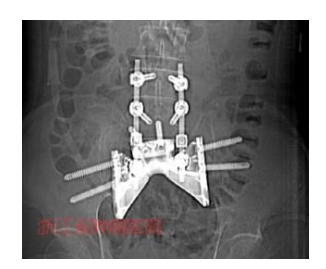

图3 术后X线片